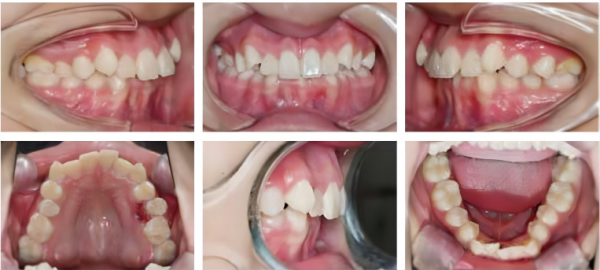

Before Treatment

Intra-oral photos

Sagittal plane issues: Class II malocclusion, deep overbite.

Vertical plane issues: Deep overbite of anterior teeth.

Horizontal plane issues: Maxillary dental arch is too wide in the midsection, while the mandibular dental arch is narrow.

Dental arch issues: Crowded dental arch, bilateral scissor bite of premolars on the left side.